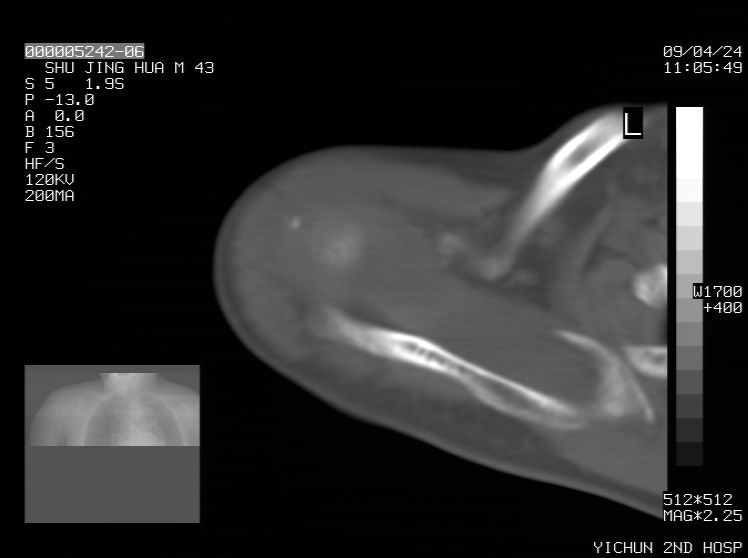

标题: CT19569:请会诊,女50岁,右肩疼痛数月 [打印本页]

标题: CT19569:请会诊,女50岁,右肩疼痛数月

钙化性肌腱炎

是指钙盐沉积在变性肌腱中的一种无菌性炎症,常见于肩关节的肩袖肌腱,引起肩部疼痛和活动受限。分为急性和慢性两种类型,急性型有肩关节突然出现急性疼痛的发作史,夜间可痛醒。